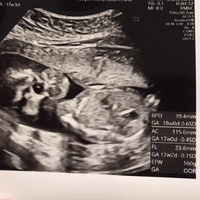

胎児の体重はどのように導き出すのか 病院の超音波検査などでエコー写真をもらうと、胎児の 「推定体重(EFW:Estimated Fetal Weight)」 などが記されていることがあります。 これはどのように計測しているのかご存知でしょうか。 · エコー写真の見方と数値の意味|お腹の赤ちゃんの体重はなぜ分かるの? 19年3月31日 19年7月31日 12分3秒 妊婦健診でわかる、胎児の身長、体重、性別。 お医者さんは、その他に赤ちゃんの何を見ているのか知っていますか? ついエコー写真に写る赤ちゃんの姿形だけに注目してしまいがちですが、実はとっても大切で、赤ちゃんの状態が色々と良く赤ちゃん (身長) 36~43cm 赤ちゃん (体重) 1100~1800g 28週0日から出産予定日まで84日 31週6日から出産予定日まで57日

エコー 写真 身長-エコー写真が色あせてしまう前にアルバムにしてみませんか? ご用意頂くお写真 メイン写真(産まれた時のお写真)1枚 エコー写真18枚(順番が分かるように) 注文書ダウンロード PDF103KB メイン写真をスタジオで撮影することも可能です · エコー写真について質問なんですが調べたところ、BPDなどは分かったのですが、ACというのが解りません。 AC 1785cmと記されて いるのですが、何の長さかさっぱり‥身長でしょうか? ご存知の方教えてくださいm(__)

9週4日 Misasi19さん 30歳 9週4日のエコー写真 Crl 頭殿長 身長 または胎嚢の大きさ 23 5mm 体重 Bpd 頭の横幅 妊娠発覚から2回目の産婦人科を受診した際のエコー写真です 1回目のときは胎嚢があり中にまるでお豆が入っているような 頭の形 嫌な予感 さよならじゃないよ また会おうね 立ち直り途中1面はタイトル、メインの記念写真、お名前、性別、誕生日時、生まれた時の身長・体重、出生場所が入ります。エコー写真側は1面に標準で12枚、13枚以上は12枚ごとに1ページ追加となり、最大60枚まで入ります。 12種類のデザインからお選びください。 仕様 名称 おなかアルバム サイズ台紙 · 身長は、エコー写真で分かるものではありませんが、部分的に大きさがわかります。 それで赤ちゃんが成長しているかを判断するのがいいと思います。 身長は、見ていると 生まれた赤ちゃんは45㎝~55センチくらいのような気がします。